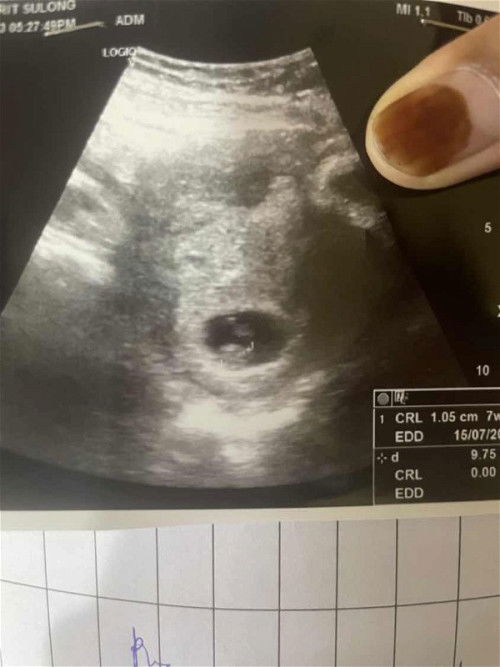

KEMBAR KE ATAU BAYANG2??

Assalam dan selamat petang.. tadi saya ada scan kandungan saya tapi saya tertanya- tanya kembar ke atau bayang2 atau uri.. doc x dpt detec lagi kembar ke atau x kene scan lg 2 minggu akn dtg..jadi mommy yg pernah preg twin boleh la share2 pengalaman supaya saya tidur dlm ketenangan